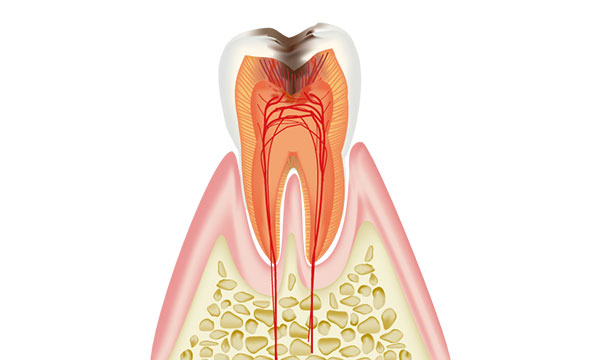

虫歯は進行の程度で5段階に分けられます。

虫歯で歯が崩壊します。神経は細菌に感染して死んでしまいます。 細菌が溜まり根の先に膿を作ります。 ここまで進行すると神経が死んでいるため痛みを感じない事が多いですが、膿が溜まる事で痛みがでる場合もあります。 治療方法は根の治療か抜歯になります。